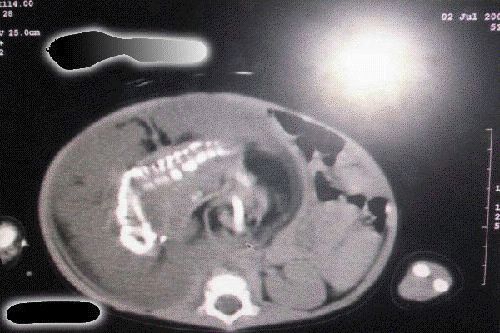

طفله تبلغ من العمر سنة واحدة وجدت حامل في المملكه العربية السعودية. ويقول الاطباء انها حالة فريدة في العالم!

ويقول التقرير : ان الأم كانت حاملا بجنينين ولكن احداهما نما داخل الآخر.